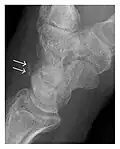

Fatigue fractures are more frequent in women which may be due to the relatively smaller bones of women. Moreover, pregnancy is a well-recognized risk factor for femoral neck fatigue fracture. While fibular and metatarsal fractures have a low risk of complications, other sites including the femoral neck, midanterior tibia, navicular, talar, and other intraarticular fractures are prone to complications such as delayed union, nonunion, and displacement. The site of the insufficiency fracture may be specific to the activity: for example, rugby and basketball players are more prone to navicular fractures, while gymnasts have a higher risk for talar fractures (Figure 7). Long distance runners are at increased risk for pelvic, tibial (Figures 8 and 9), and fibular fractures. In the military, calcaneus (Figure 10) and metatarsals are the most commonly cited injuries, especially in new recruits. Billiard players are at risk for upper limb fractures (Figure 11).[1]

a

b

Figure 9: Proximal metaphyseal fatigue fracture of the tibia in a 27-year-old recent male military recruit. (a) Anteroposterior radiograph is within normal limits. (b) Coronal T1-weighted MR image shows a marked linear hypoattenuation along the medial tibial metaphysis (arrow) surrounded by diffuse hypointensity in keeping with posttraumatic edema.[1]